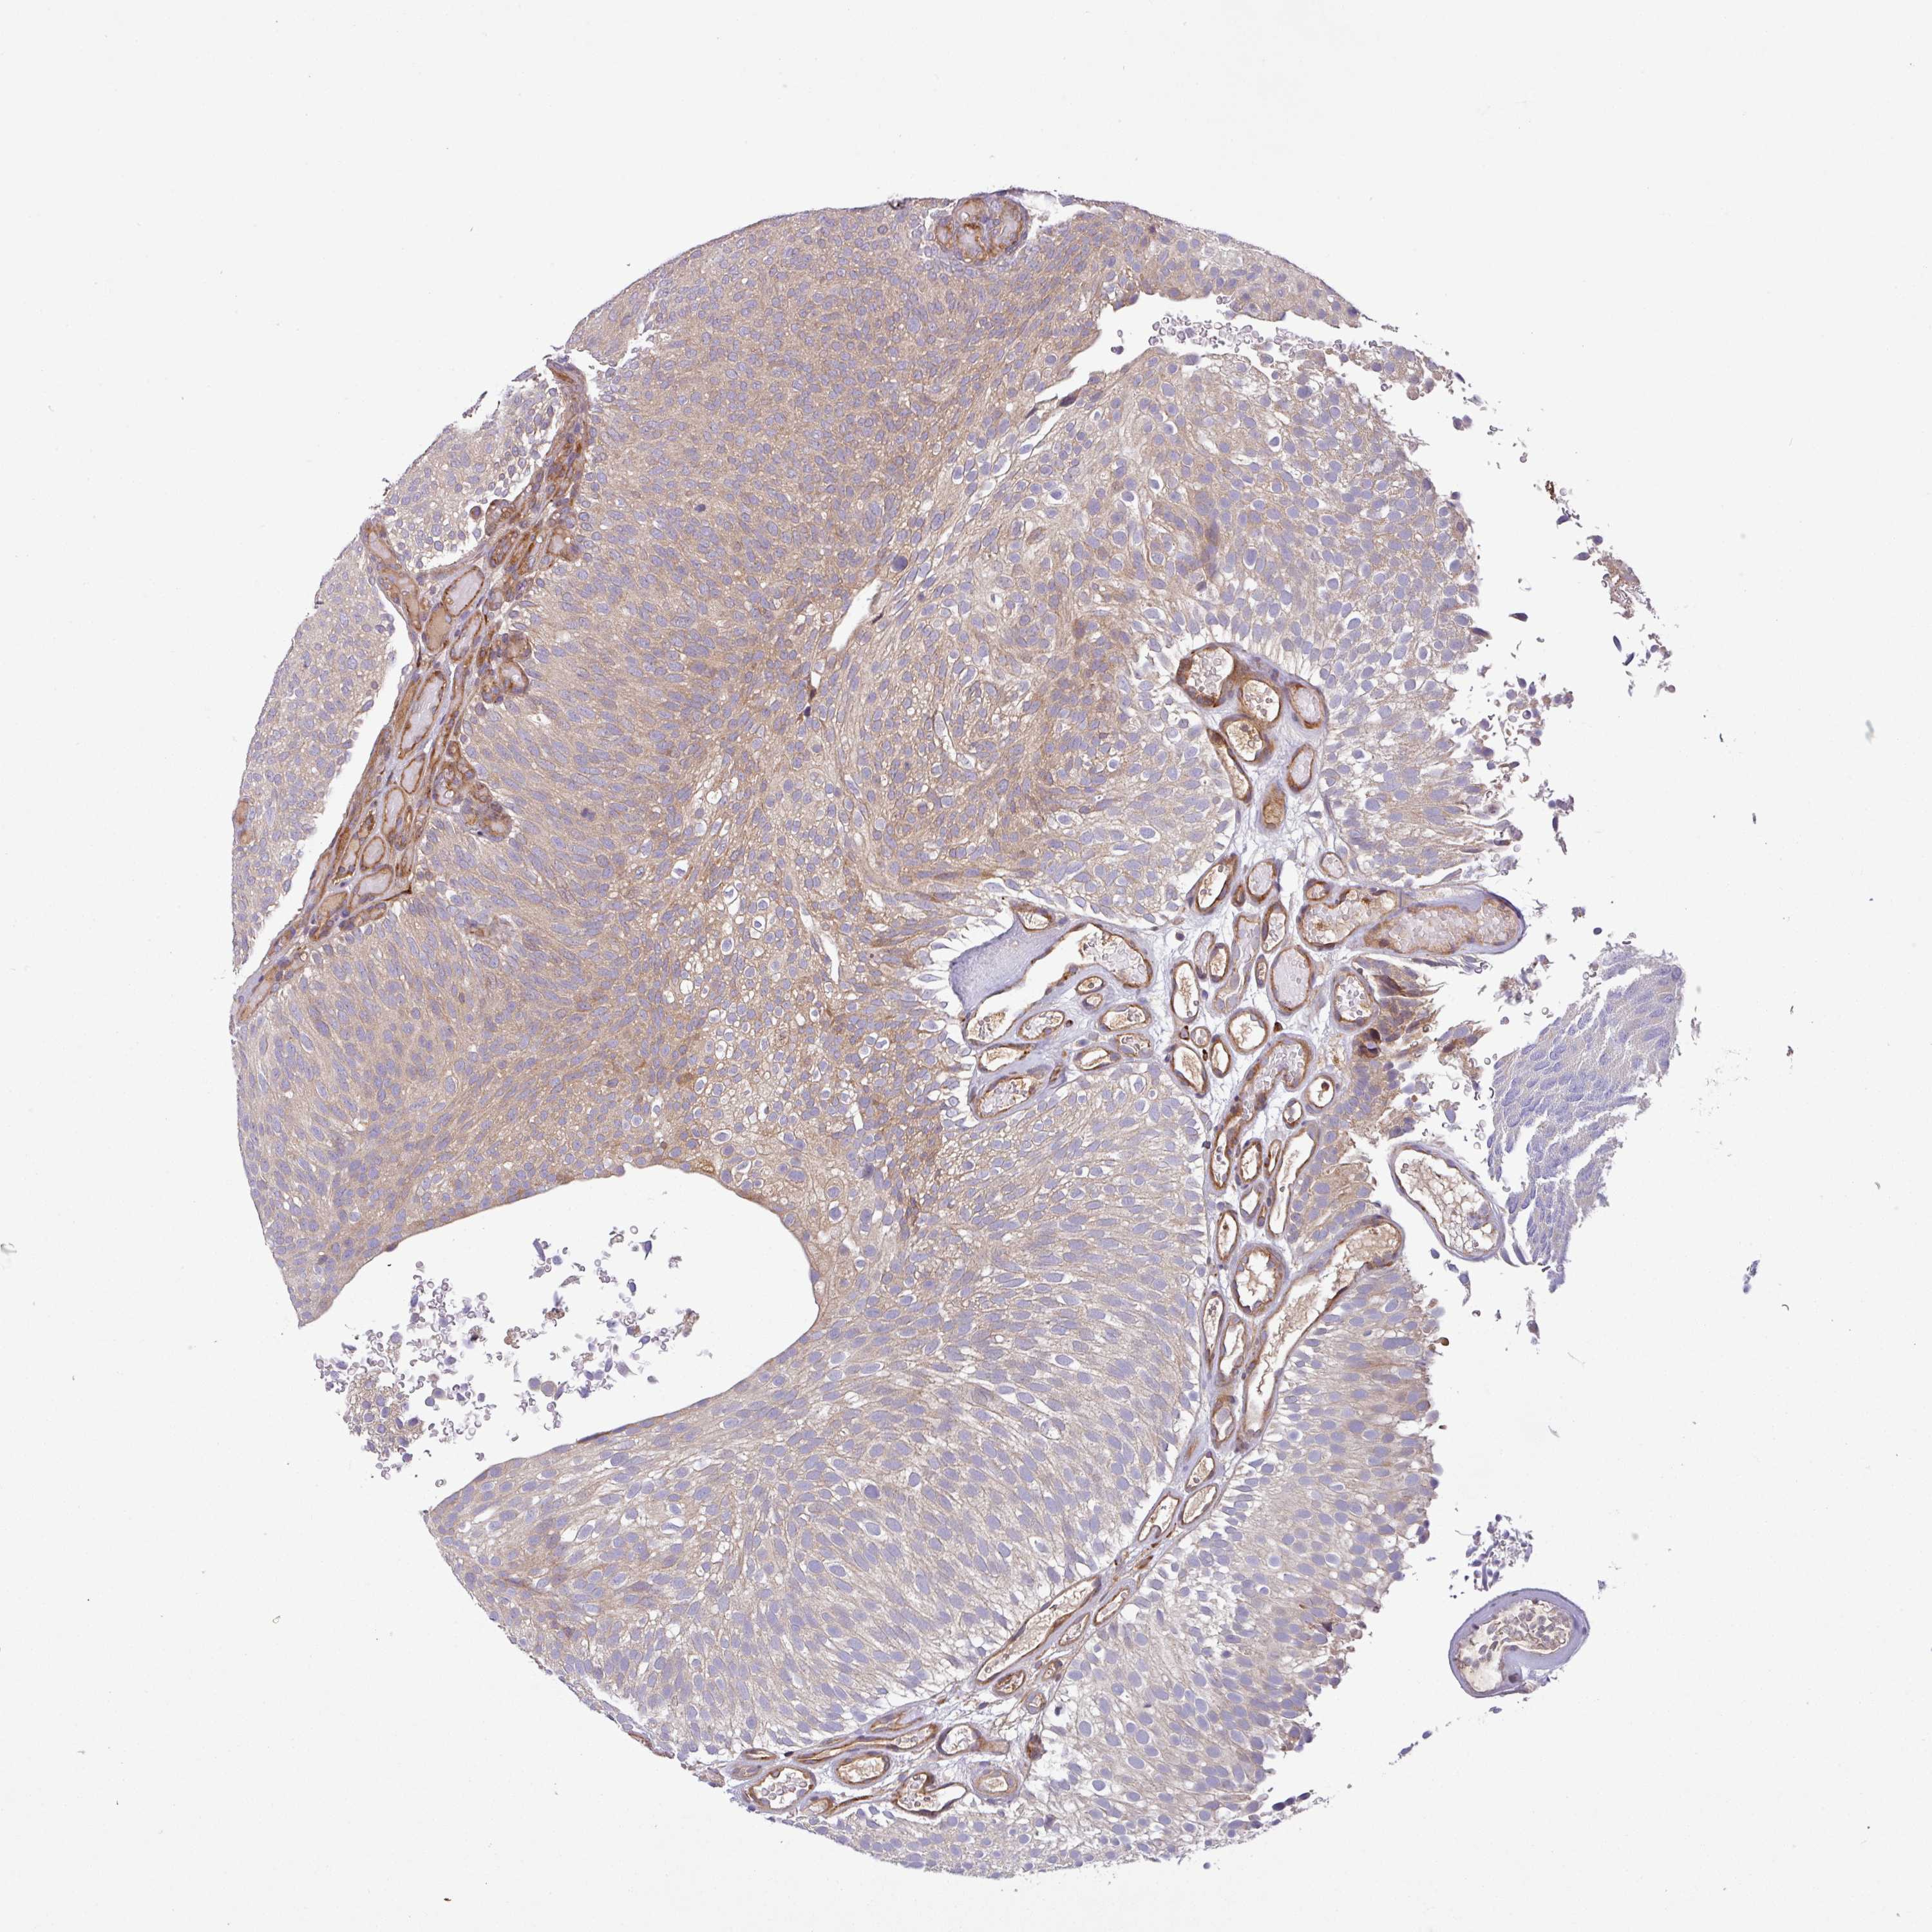

UROTHELIAL CANCER - Protein expressioni

A mouse-over function shows sample information and annotation data. Click on an image to view it in a full screen mode. Samples can be filtered based on level of antibody staining by selecting one or several of the following categories: high, medium, low and not detected. The assay and annotation is described here.

Note that samples used for immunohistochemistry by the Human Protein Atlas do not correspond to samples in the TCGA dataset.

Antibody stainingi

Antibody staining in the annotated cell types in the current human tissue is reported as not detected, low, medium, or high, based on conventional immunohistochemistry profiling in selected tissues. This score is based on the combination of the staining intensity and fraction of stained cells.

Each image is clickable and will lead to virtual microscopy that enables deeper exploration of all samples and also displays staining intensity scores, fraction scores and subcellular localization as well as patient and tissue information for each sample.

Antibody HPA051148

Staining

High

Medium

Low

Not detected

Intensity

Strong

Moderate

Weak

Negative

Quantity

>75%

75%-25%

<25%

None

Location

Nuclear

Cytoplasmic/membranous

Cytoplasmic/membranous,nuclear

Urothelial carcinoma, High grade

Urothelial carcinoma, Low grade